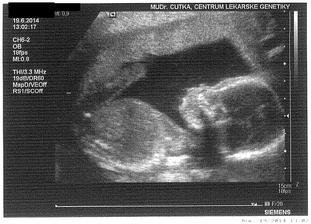

* 19.6.2014 - UZ v genetickém centru ve 20.tt - miminko je ukázkové - 25cm, 290g a odpovídá poslední MS. a máme potvrzenou holku 🙂 Je nádherná a máme i krásné video 🙂